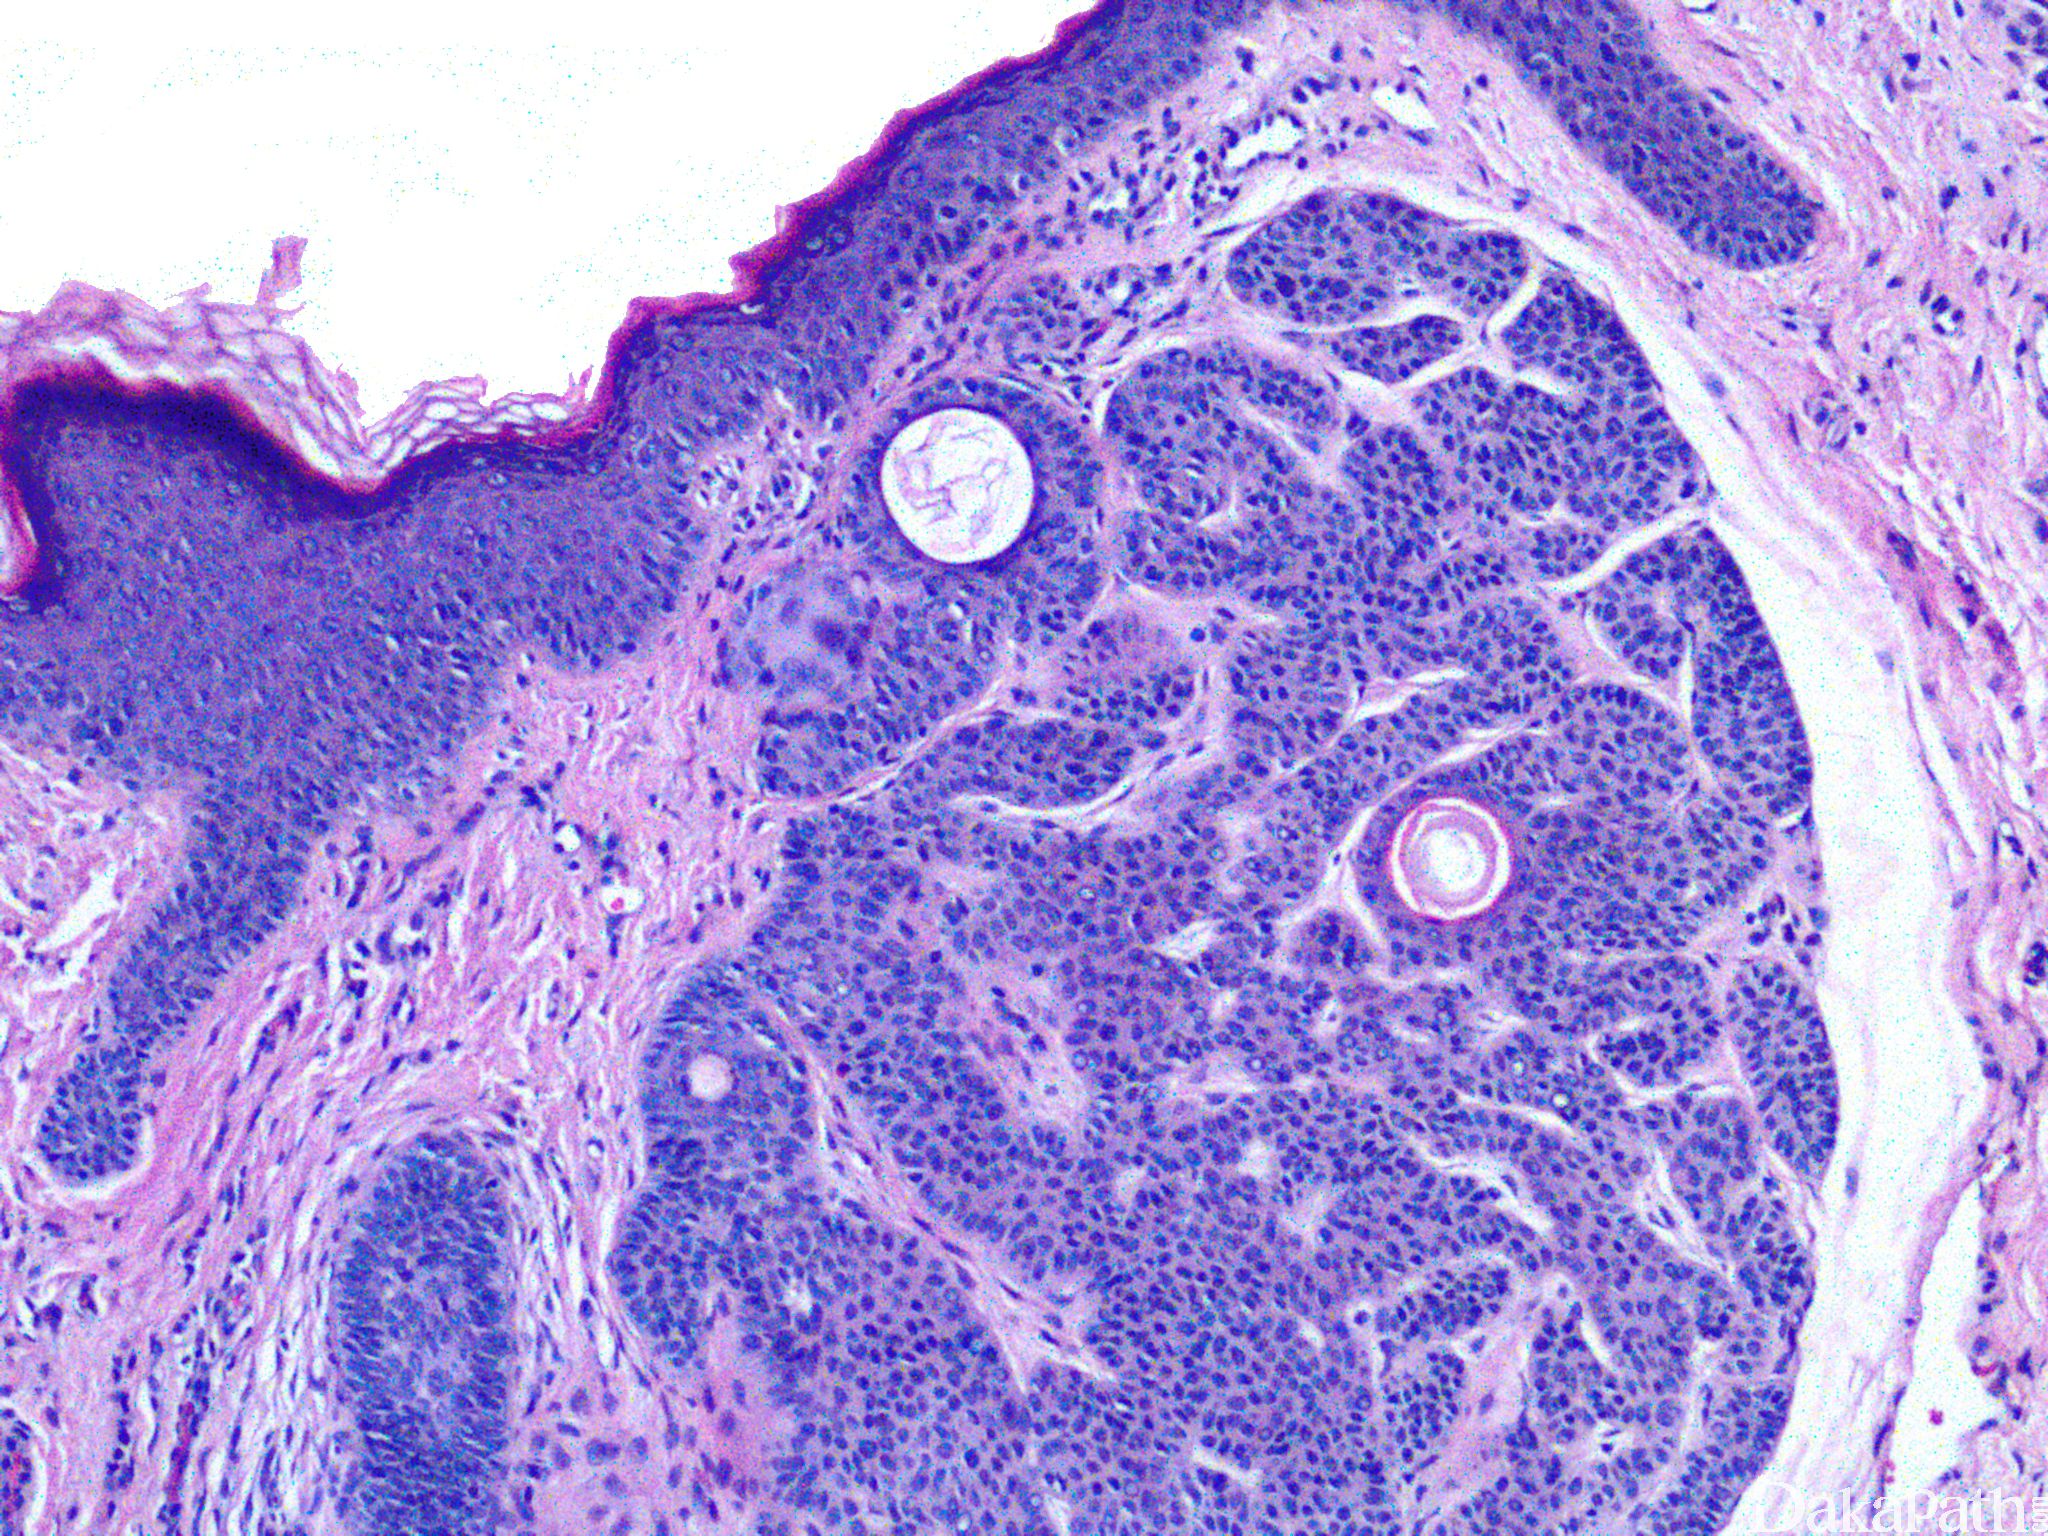

病变界限界清,镜下见真皮内基底样细胞增生,呈细条带和分支条索状互相吻合,常与表皮相连或与毛囊邻近或相连;

基底样细胞形态温和,核分裂缺如或罕见;

可见小的角质囊肿;

细胞索被机化的纤维基质包围。